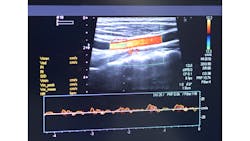

While 2D ultrasound imaging can provide images in real time even if the target moves, 3D ultrasound imaging is much more sensitive to changes in movement. Repositioning limbs, for example, may be necessary to make different parts of a limb available to the ultrasound probe in order to image an entire artery. The angle of the 2D image changes from its original position, making it difficult to stitch the images together into a 3D representation.

Robotic ultrasound systems (RUSS) produce high quality images by precisely controlling the contact force and orientation of the ultrasound probe. Combining robot arms with depth cameras to determine optimal probe position increases the accuracy of the scan. This is still not effective for 3D imaging because this system also cannot account for movement of the scan target.

Because the system can assign 3D coordinates to images during the scan, even if the limb moves, the system can compensate for the movement and stitch the images together as if the limb movement never took place. This allows for creating accurate 3D scan data. Testing demonstrated that the system compensates for up to 40° of target rotation.